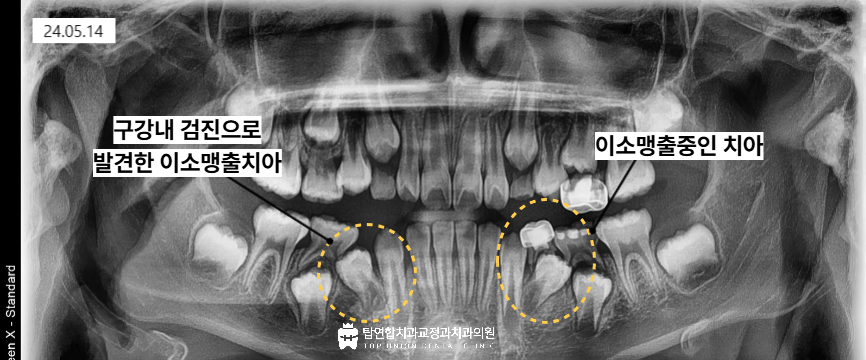

구강 내 검진을 해보니 아래쪽의 첫번째 작은 어금니가 비뚤어져서

비정상적인 맹출 경로로 인해 나오지 못하고 걸려있는 모습이었습니다.

정확한 상태 확인을 위해서 전체 파노라마 x-ray를 촬영해 보았습니다.

구강 내 검진을 통해서 발견한 이소맹출치아는

뒤쪽의 유구치 쪽으로 기울어져 있는 것을 확인하였습니다.

그런데 동시에 반대편 왼쪽의 첫번째 작은 어금니 방향도

뒤쪽 방향을 향해있는 것을 발견하였습니다.

동시에 뒤쪽으로 치아가 기울어지면서 발생한 공간으로 인해

앞니에는 치아 사이가 벌어지는 치간이개가 관찰되었습니다.